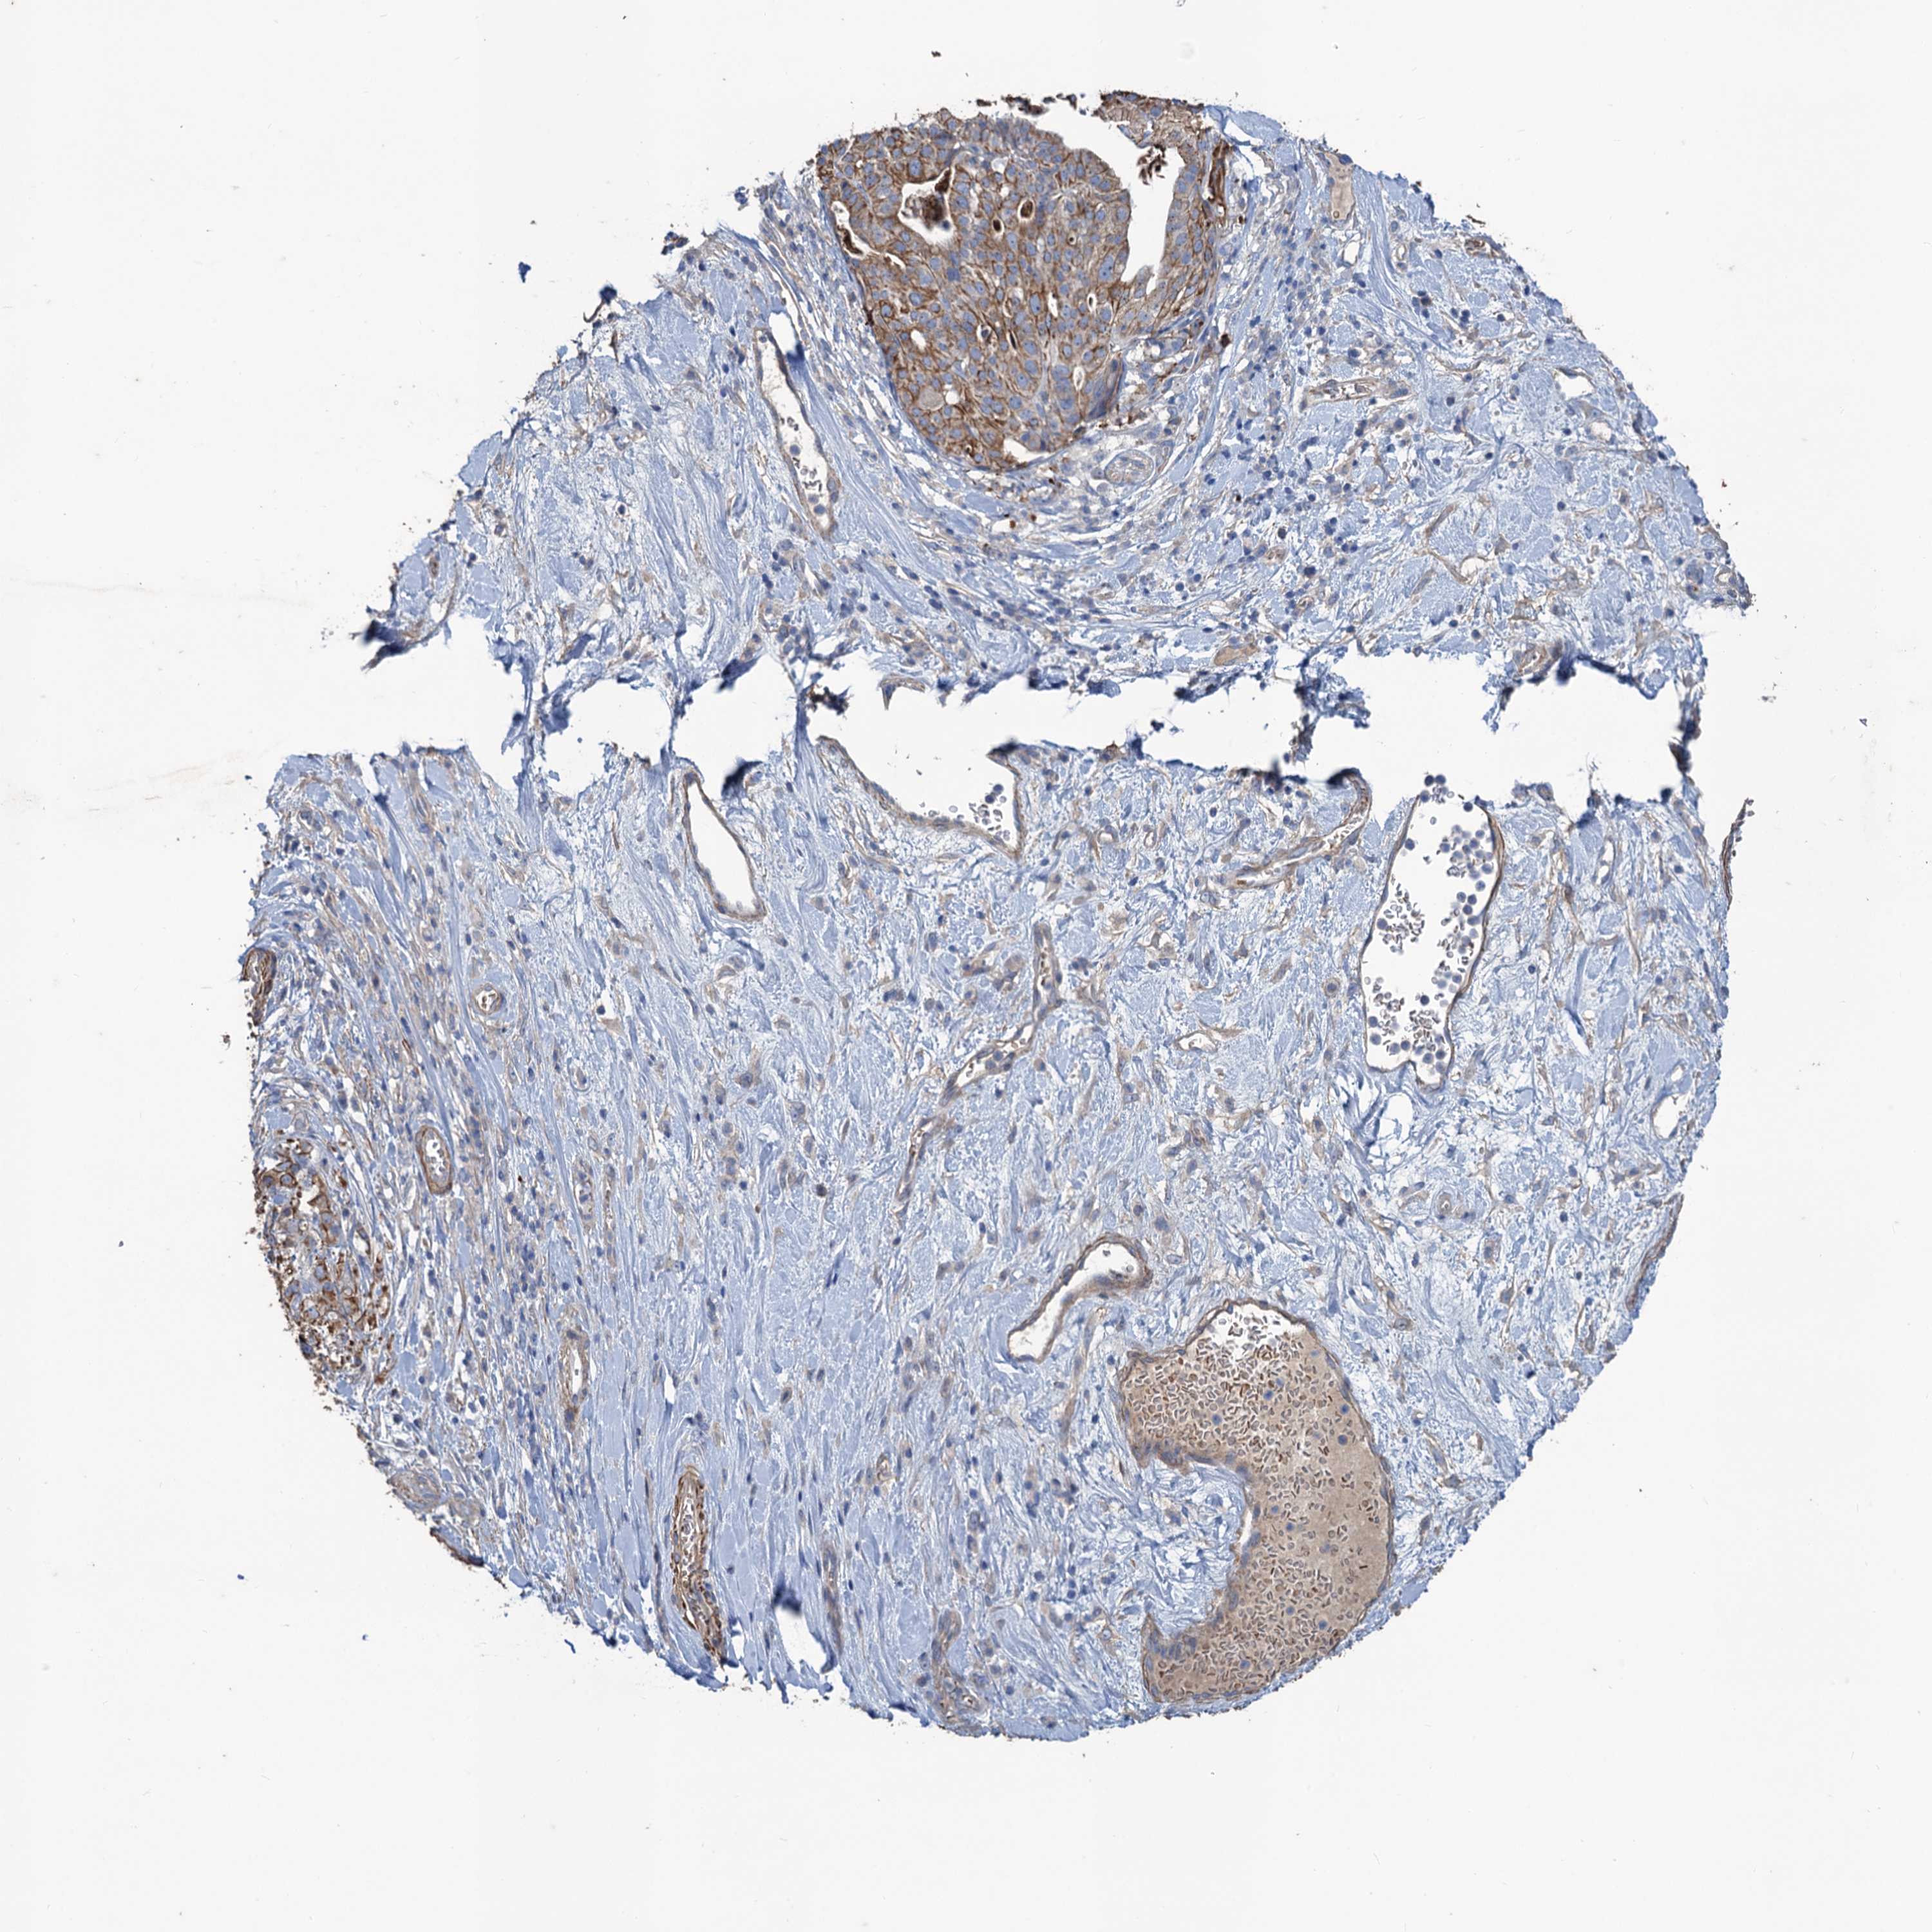

STOMACH CANCER - Protein expressioni

A mouse-over function shows sample information and annotation data. Click on an image to view it in a full screen mode. Samples can be filtered based on level of antibody staining by selecting one or several of the following categories: high, medium, low and not detected. The assay and annotation is described here.

Note that samples used for immunohistochemistry by the Human Protein Atlas do not correspond to samples in the TCGA dataset.

Antibody stainingi

Antibody staining in the annotated cell types in the current human tissue is reported as not detected, low, medium, or high, based on conventional immunohistochemistry profiling in selected tissues. This score is based on the combination of the staining intensity and fraction of stained cells.

Each image is clickable and will lead to virtual microscopy that enables deeper exploration of all samples and also displays staining intensity scores, fraction scores and subcellular localization as well as patient and tissue information for each sample.

Antibody HPA040574

Antibody HPA047804

Staining

High

Medium

Low

Not detected

Intensity

Strong

Moderate

Weak

Negative

Quantity

>75%

75%-25%

<25%

None

Location

Nuclear

Cytoplasmic/membranous

Cytoplasmic/membranous,nuclear

Adenocarcinoma, NOS

Adenocarcinoma, High grade